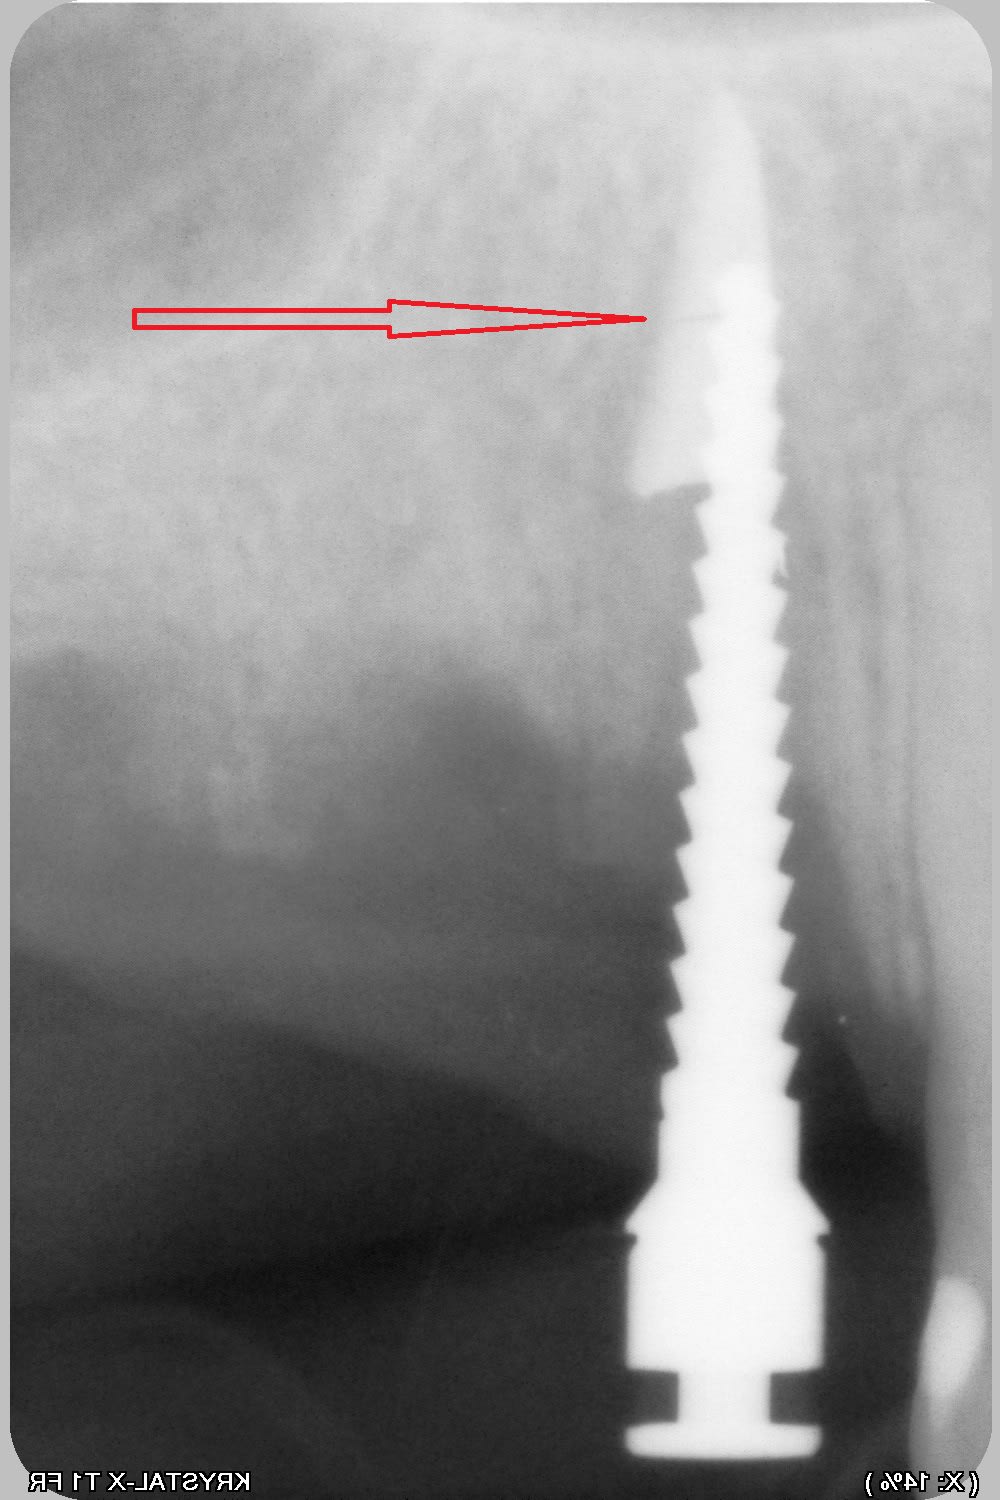

une petite erreur, de plus en pensant mobiliser 11 avec un spreader...lame 11 cassée en deux partie...

de nouveau lame 15, sonde 17, luxotome...et ça vient....mince il reste la pointe....je ne veux pas risquer de l'envoyer plus haut donc je me dis qu'elle ne gênera pas.